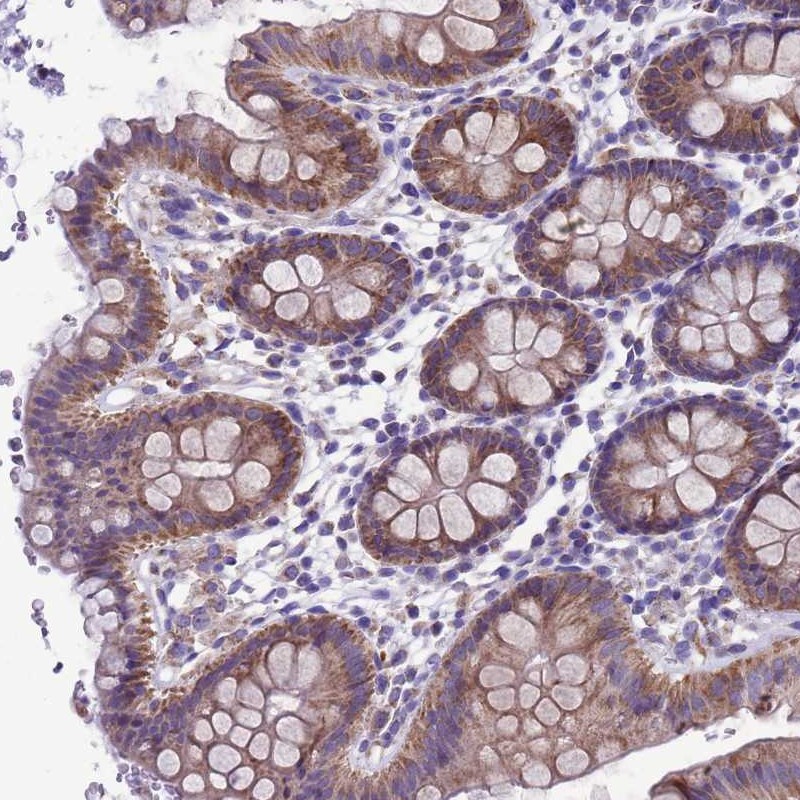

Immunohistochemical staining of human colon shows moderate cytoplasmic positivity in glandular cells.